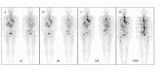

从近日在连云港结束的中国核学会近距离治疗与智慧放疗分会2025年学术年会上传出好消息:历经10年建设、5年临床实践,甘肃省武威肿瘤医院武威重离子中心交出了一份振奋人心的中国答卷。在恶性肿瘤治疗领域,其临床疗效实现突破性跃升:针对难治性高级别脑胶质瘤,患者中位无进展生存期(即在可评估的患者中,50%的患者能达到的无进展生存期)较国际公认的光子Stupp研究近乎翻倍,中位生存期更是提升13.4个月,突破至28个月;面对III期局部晚期肺癌,2年总... 2025-12-11 核医学放射诊疗